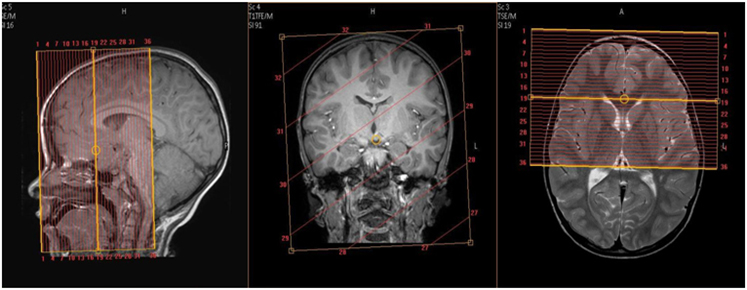

Whole Brain Sagittal Coverage: Angle to interhemispheric fissure. Cover at least 1cm above vertex through skull base. Cover entire nose.

Whole Brain Axial Coverage: Angle to corpus callosum. Cover at least 1cm above vertex through skull base. Cover entire nose.